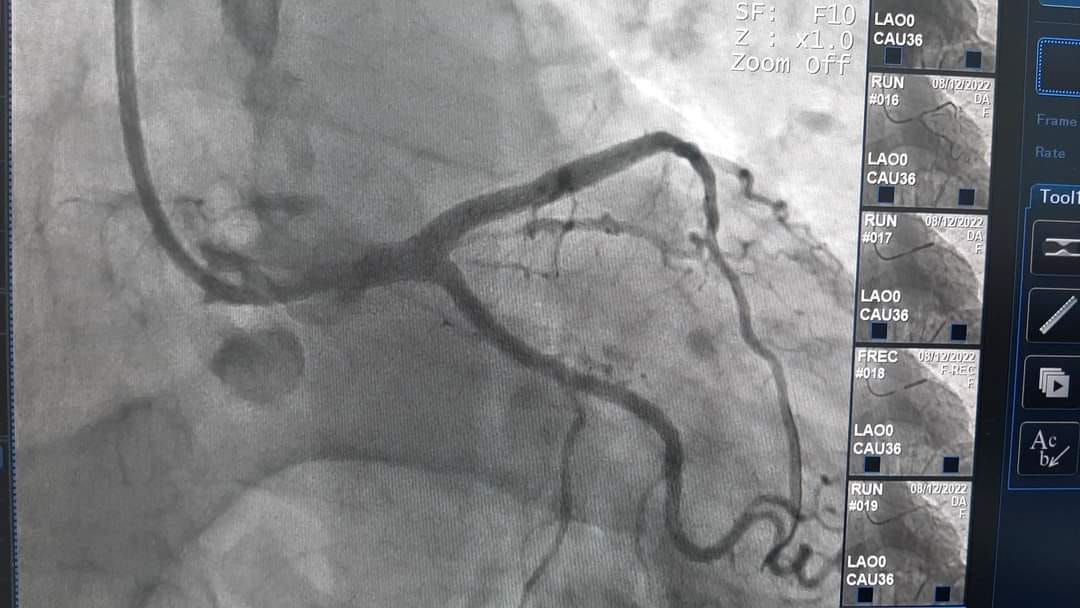

Пацієнт поступив до медзакладу з симптомами нестабільної стенокардії та був скерований кардіологами на коронарографію. У лівій артерії чоловіка виявили атеросклеротичну бляшку з критичним звуженням. Оптична когерентна томографія показала розрив, який загрожував великим інфарктом. Завдяки цьому медики вчасно провели необхідне втручання.